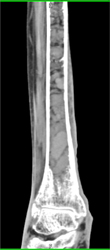

Fracture and Dislocation of the Ankle